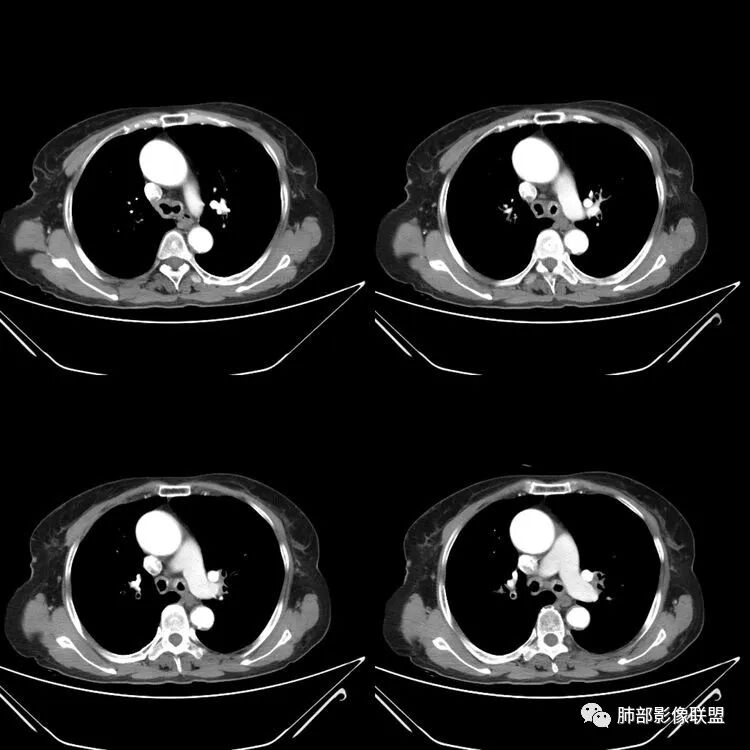

患者,女,64岁,反复咳嗽、咳痰、胸闷10年,加重2周患者10余年来每当受凉感冒出现咳嗽、咳痰、胸闷,有时痰中带血,输液治疗(具体不详)可好转。既往有声带肥厚手术病史。CT示气管、主支气管及分支支气管管壁弥漫性增厚累及膜部,局部伴钙化,管腔狭窄,考虑淀粉样变性

患者,女,64岁,反复咳嗽、咳痰、胸闷10年,加重2周。气管支气管及两肺下叶 支气管弥漫性的环状增厚,管腔扩张,管腔感觉比较松弛。第一感觉,气管支气管淀粉样变。鉴别诊断,1、支气管内膜结核,肺内散在一些支气管的播散病灶,粟粒结节为主,形态比较单一。2、复发性的多软骨炎,就得了解一下其他部位,有没有多个部位的软骨炎。这个病人右侧胸廓缩小,升主动脉明显的扩张,其横径明显的超过了降主动脉。

征象很明确

弥漫支气管壁增厚,膜部受累

声带肥厚——受累

隐约见钙化

南边:肺部有肺气肿支气管腔狭窄淀粉样变性?复发性多软骨炎?血管炎?慢支?结核?曲霉菌?南边:一般还是淀粉样变性与复发性多软骨炎鉴别其次就是支气管骨化症,但是骨化下朝上,且壁结节状钙化明显,本例不太支持。至于结核、曲霉菌?1.结核,一般不会这么广泛,支气管壁狭窄后扩张2.曲霉菌可以这么广泛,但是支气管壁管腔扩张,而且附近脂肪间隙有炎性反应,不太支持;3.血管炎,一般合并肺内有病灶,但是声带受累,放待排;4.软骨炎一般全身受累,例如耳廓等;而且膜部不受累,不太支持;倾向于淀粉样变性;淀粉分很多型,气管支气管是最常见的。尘缘:影像上生理性钙化与支气管骨化无法区别,镜检也不好鉴别,需要依赖活检,看粘膜中是否合并炎性改变(淋巴细胞,组织细胞等炎性细胞侵润)来鉴别Coke with ice:经常看到的这种是老年性肺改变,又称年龄相关肺改变。气管和支气管弥漫性软骨钙化,常见老年女性。尘缘:支气管骨化症很罕见的,所以绝大多数还是生理性钙化。对于老年人,无临床症状的钙化,还是基本上都是生理性钙化,无临床意义。大雄:如果管壁钙化伴明显增厚 影像还是提示一下建议支气管镜稳妥些

1.气管支气管型

①气管支气管壁增厚,形成粘膜下斑块与结节

②管腔广泛狭窄、闭塞

③管壁钙化

④膜部受累(具有重要鉴别意义)